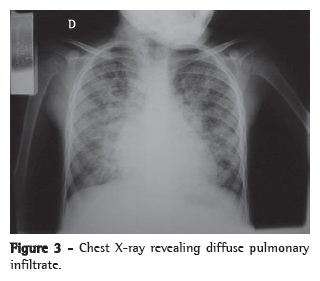

Figures 3 and 4 illustrate the use of the BAL fluid for the diagnosis of lung diseases, depicting the radiologic image (Figure 3) and the BAL fluid (Figure 4) that aided in the diagnosis of pulmonary hemosiderosis in a

child with a history of hemoptysis and iron-deficiency anemia.